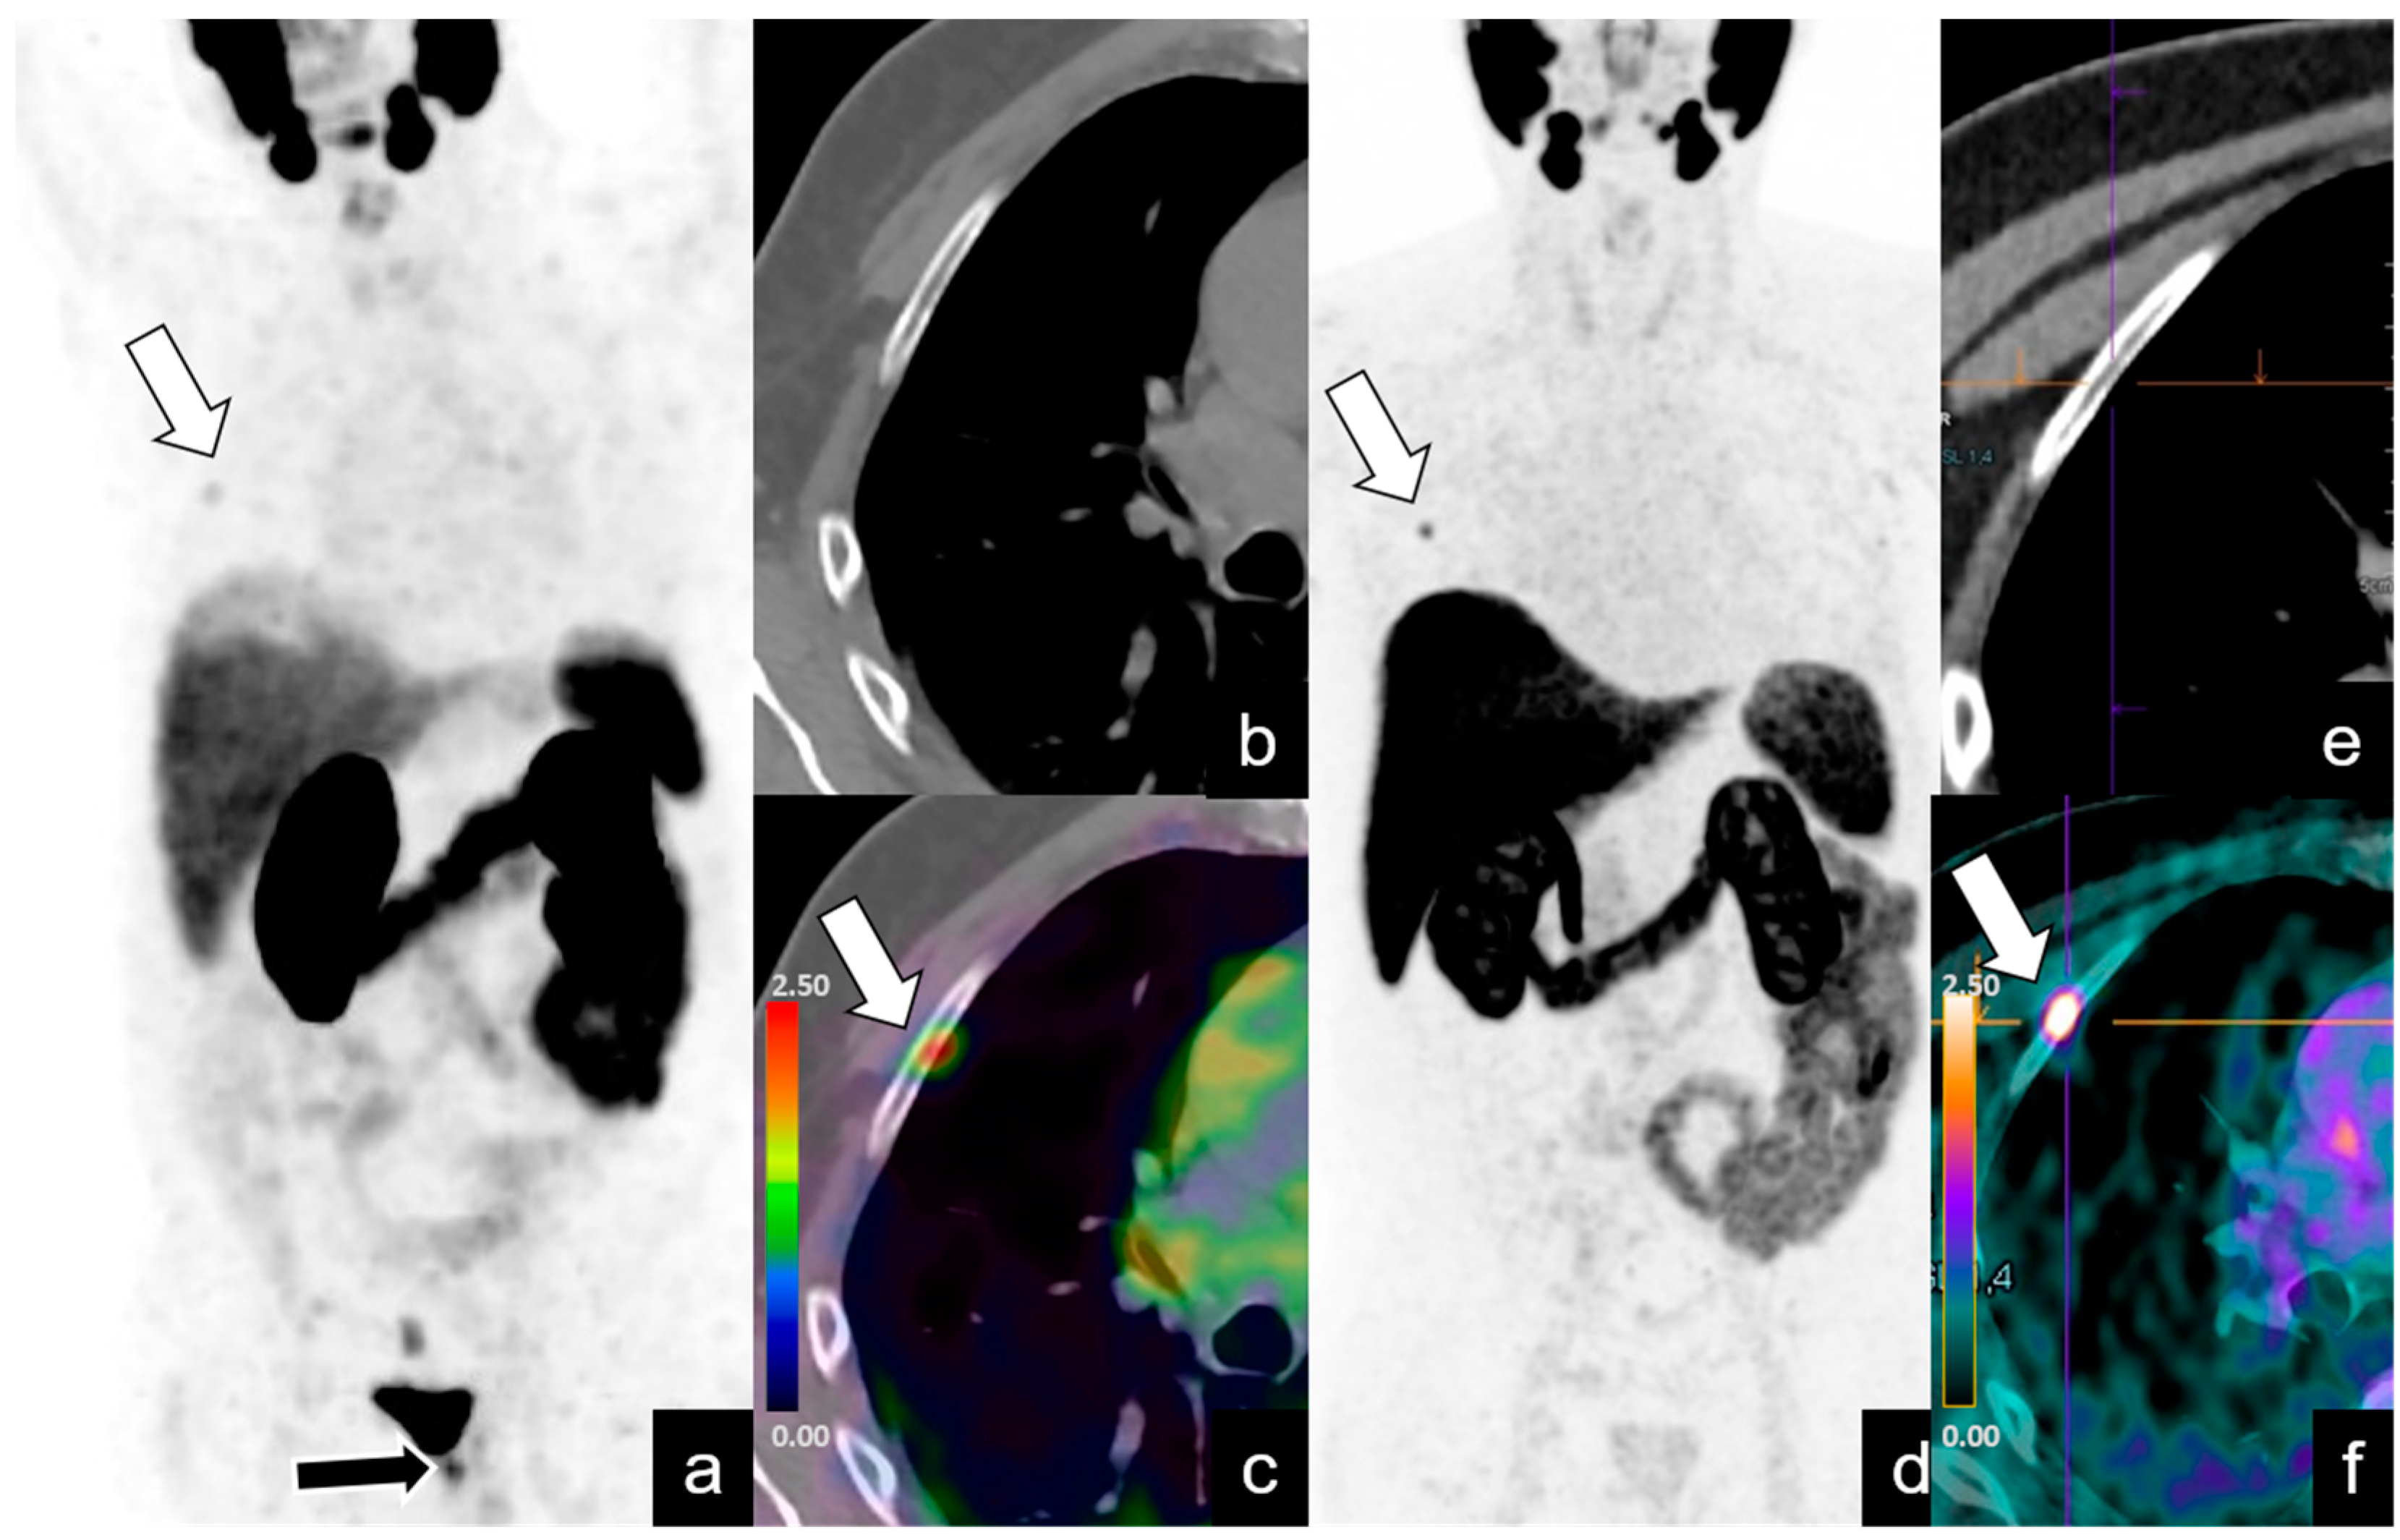

| Abdominopelvic | 39/128 (30%) | 24 | 1–73 | 7.3 | 2–19 |

| Supradiaphragmatic | 4/128 (3%) | 27.2 | 3–60 | 18.5 | 15–22 |